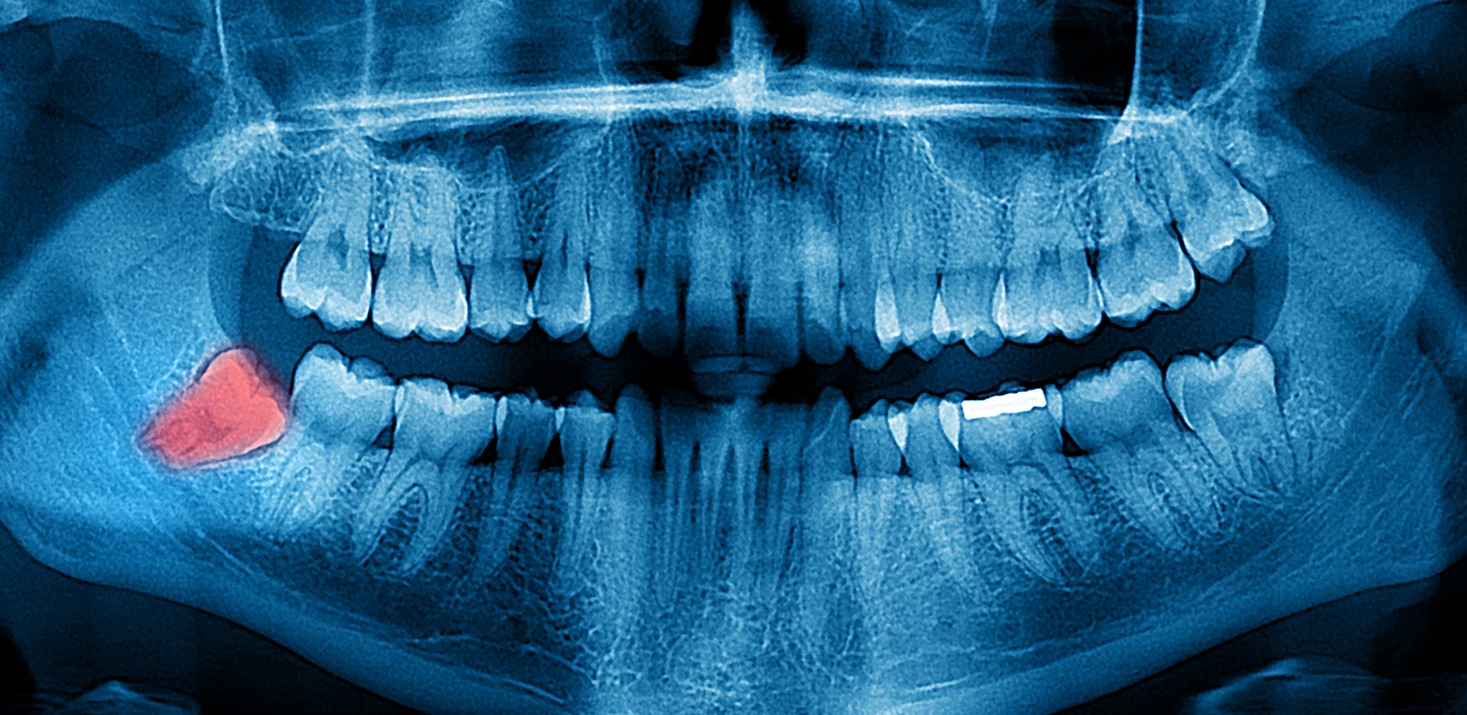

- Панорамные снимки (ОПТГ): Отображают всю челюсть и зубы на одном снимке. Помогают оценить общее состояние ротовой полости.

- Оценить состояние корней зубов: Определить наличие воспалений, кист и других патологий.

- Выявить скрытые проблемы: Обнаружить зубы мудрости, которые еще не прорезались, и оценить их влияние на соседние зубы.